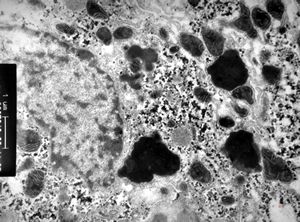

M,15y. | Wilson disease - megamitochondria

M,15y. | Wilson disease

F,14y. | megamitochondria - Wilson disease

F,6y. | Wilson disease - megamitochondrion

F,6y. | Wilson disease